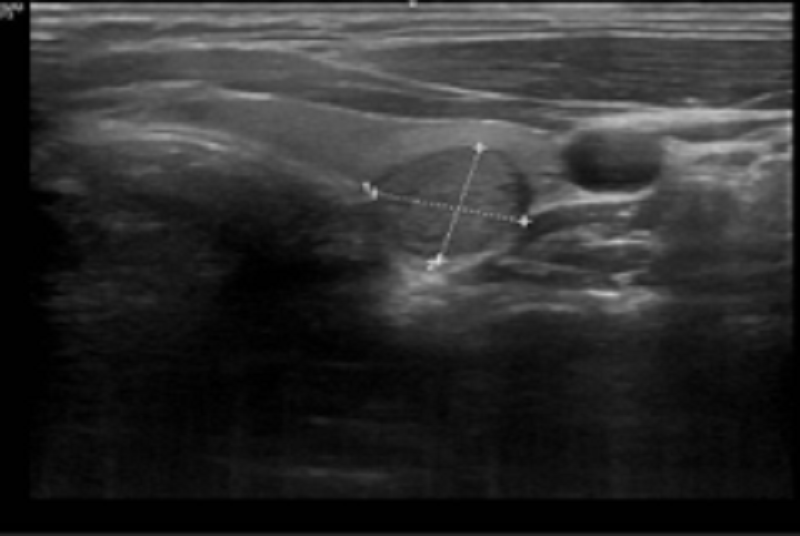

Siêu âm tuyến giáp ghi phát hiện có nhân giảm âm - dấu hiệu nghi ngờ ác tính

Trong đó, đáng lưu ý kết quả siêu âm tuyến giáp nhu mô có nhân giảm âm kích thước 10.4 x 11.6 mm, chiều cao lớn hơn chiều rộng - dấu hiệu nghi ngờ ác tính, vị trí nhân sát vỏ bao tuyến giáp. Vì vậy, bác sĩ chỉ định bệnh nhân chọc hút tế bào bằng kim nhỏ (FNA).

- Siêu âm tuyến giáp: Là phương pháp quan trọng hàng đầu trong phát hiện và đánh giá nhân giáp qua việc xác định chính xác kích thước, vị trí, cấu trúc và các đặc điểm nghi ngờ của nhân như độ phản âm, bờ viền, tình trạng vôi hóa hay mức độ tăng sinh mạch máu, kết quả được phân loại theo ACR TIRADS 2017 với TIRADS từ 1 tới 5. Bên cạnh đó, siêu âm còn đóng vai trò hướng dẫn các thủ thuật như chọc hút tế bào (FNA), giúp tăng độ chính xác và giảm tỷ lệ lấy mẫu không đạt yêu cầu. Đồng thời, đây cũng là công cụ hữu ích trong theo dõi tiến triển bệnh sau điều trị.